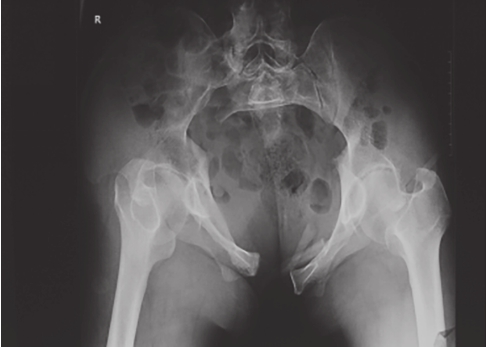

骶髂关节脱位及髂骨翼后部直线骨折易于识别,脱位及骨折移位程度容易测量;骶孔直线骨折由于骶髂关节并无脱位,骶孔外缘骨折线又不清楚,易被忽略。但仔细比较两侧髂骨高度及骶骨侧块高度,则可见S 1 侧块有骨折线。以L 5 横突为标准,骨折侧的髂骨翼上移。骶骨侧块更接近L 5 横突。如L 5 横突有骨折并向上移位,则说明是此类骨折(图2-8)。

图2-8 骨盆后环损伤X线片

可见耻骨联合分离、耻骨支骨折,提示骨盆前环损伤;髂骨骨折、骶髂关节分离,骶骨骨折,提示后环损伤;L

5

横突骨折(箭头所示)、骶棘韧带和骶结节韧带撕脱骨折,提示骨盆骨折不稳,移位较大。